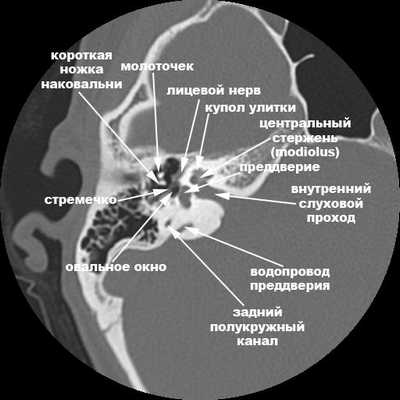

Нормальная анатомия уха

КТ-анатомия височных костей

Компьютерная томография височных костей в норме показывает следующие анатомические структуры:

— Что показывает КТ височных костей?

— На КТ-снимке мы наблюдаем структуры наружного, среднего и внутреннего уха (слуховые косточки, конфигурацию слухового прохода). Кроме того, можно оценить костные элементы, а также воздушные полости височной кости на предмет нарушения их пневматизации (заполнения воздухом). На основании этих данных мы делаем вывод, являются ли выявленные изменения причиной недуга, который беспокоит пациента.